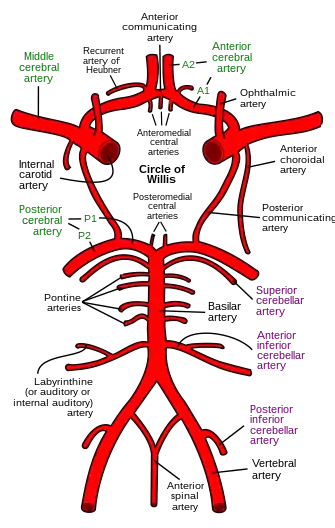

Blood supply

Blood supply to the brain is normally divided into anterior and posterior segments, relating to the different arteries that supply the brain. The two main pairs of arteries are the Internal carotid arteries (supply the anterior brain) and vertebral arteries (supplying the brainstem and posterior brain).[2]. The anterior and posterior cerebral circulations are interconnected via bilateral posterior communicating arteries. They are part of the circle of Willis, which provides backup circulation to the brain. In case one of the supply arteries is occluded, the circle of Willis provides interconnections between the anterior and the posterior cerebral circulation along the floor of the cerebral vault, providing blood to tissues that would otherwise become ischemic.[3]

Anterior cerebral circulation

The anterior cerebral circulation is the blood supply to the anterior portion of the brain including eyes. It is supplied by the following arteries:

- Internal carotid arteries: These large arteries are the medial branches of the common carotid arteries which enter the skull, as opposed to the external carotid branches which supply the facial tissues; the internal carotid artery branches into the anterior cerebral artery and continues to form the middle cerebral artery. [4]

- Anterior cerebral artery (ACA)

- Anterior communicating artery: Connects both anterior cerebral arteries, within and along the floor of the cerebral vault.

- Middle cerebral artery (MCA)

Posterior cerebral circulation

The posterior cerebral circulation is the blood supply to the posterior portion of the brain, including the occipital lobes, cerebellum and brainstem. It is supplied by the following arteries:

- Vertebral arteries: These smaller arteries branch from the subclavian arteries which primarily supply the shoulders, lateral chest, and arms. Within the cranium the two vertebral arteries fuse into the basilar artery.

- Basilar artery: Supplies the midbrain, cerebellum, and usually branches into the posterior cerebral artery

- Posterior cerebral artery (PCA)

- Posterior communicating artery